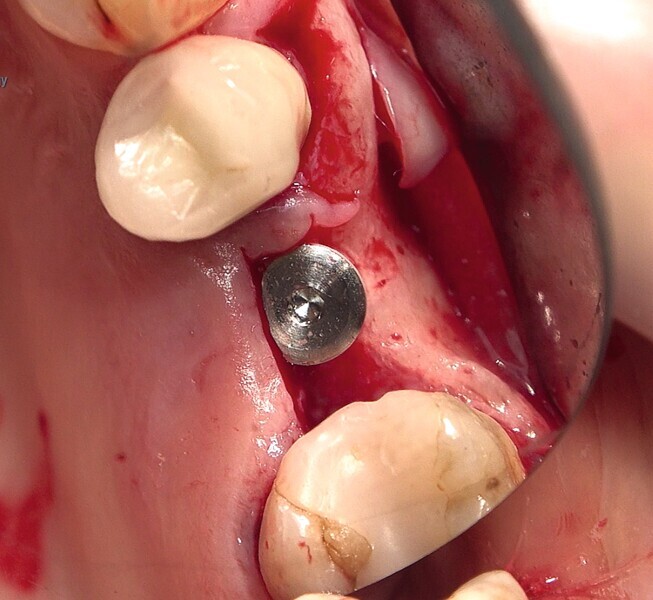

Fig. 38 : Pose de l’implant deux pièces en céramique au niveau tissulaire.

Fig. 39 : Pose de l’implant deux pièces en céramique au niveau tissulaire.

Fig. 40 : Pose de l’implant deux pièces en céramique au niveau tissulaire.

Un patient présentant un défaut infraosseux s’est présenté au cabinet dentaire avec le souhait explicite d’un traitement par un implant en zircone, pour remplacer l’une de ses molaires. Un implant deux pièces en zircone a donc été posé et le défaut infra-osseux a été traité dans le même temps, au moyen d’une allogreffe osseuse et du dérivé de matrice amélaire Emdogain (Straumann). La mise en charge n’a pas été réalisée à ce stade (Figs. 35–45).